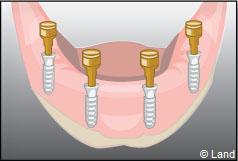

Les implants peuvent aussi servir à stabiliser un appareil amovible au maxillaire supérieur comme au maxillaire inférieur. Dans ce cas, les implants retiennent la prothèse amovible par des systèmes d’attachement.

Deux techniques sont possibles. Elles font appel à la barre de rétention ou aux boutons-pressions.

Exemple d’une réhabilitation complète implantaire